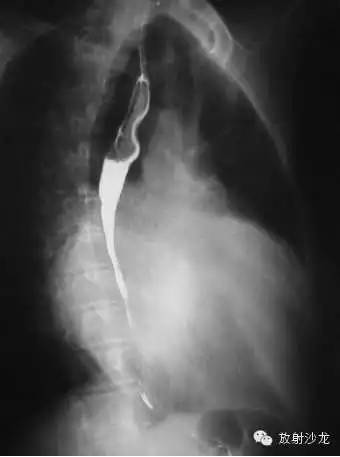

2、左前斜位:心后缘向后下延伸与脊柱重叠,室间沟前下移。

3、侧位:食道前间隙消失,心后间隙变窄。